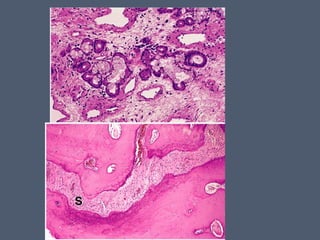

• #23 La mucosa respirratoia es llamada pituitaria roja ya que esta muy vascularizada. Es un epitelio cilindrico pseudoestratificado ciliado que posee gran cantidad de cel caliciformes. Este epitelio descansa en una lamina basal e inferior a ella el tejido conectivo donde hay glandulas de secrecion seroso y mucoso( mixto)

• #24 MUCOSA RESPIRATORIA DE LA NARIZ, CON CEL ciliadas predominantemente, celulas caliciformes de citoplasma claro, y celulas basales delineando la lamina basal.

• #26 15.44 glandulas nasales seromucinosas con sus ductos. Cel serosas cln citoplasma tincion oscura. Fig 15.48 septum nsasal, bordes paralelos de el vomer y maxilar estan conectados, en medio de una trama de fibras de colaqeno que amplian el hueso.